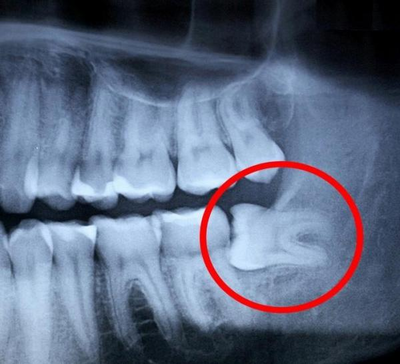

Вердикт после рентгена - удалять все 4, а сейчас мне предложили сделать разрез, чтобы не скапливалась еда под образовавшимся капюшоном. Я отказалась - через пару дней предстояли ГОСы, хотелось нормально разговаривать. Запись на 2 талона на раннее утро (удаление сложное, зубы "лежат") через 5 дней, пока поживу на обезболивающим. Как ни странно, оно не понадобилось, зубы болеть прекратили. Видимо, это было просто первое напоминание от зубов мудрости о себе.